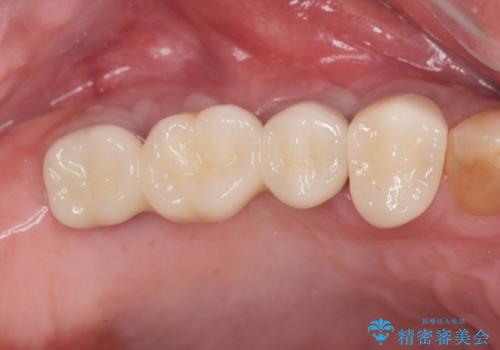

- 106.7万円 (インプラント×2 アバットメント×2 ジルコニアクラウン×3 骨造成 )費用は治療当時の料金となります

骨の造成、歯肉を整えたことで、術前山形にえぐれていた歯肉形の態はなだらかになり清掃しやすい状態へと整備することができました。